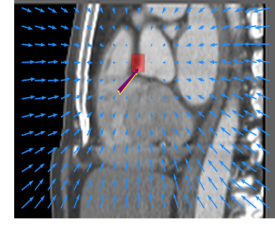

Finally, the proposed network was evaluated for the detection of five additional landmarks: the left coronary ostium, the bifurcation of the LM into the LAD and the LCx, and the origin of the left, non-coronary, and right aortic valve commissures (see Fig. 2). Fig 3 shows vector fields visualizing the predicted displacement vectors in three viewing planes in an image from the test set (for more results, see Appendix). Table 3 lists the Euclidean distance errors between the predicted landmark locations and the reference landmark locations. In addition, box-and-whiskers plots are shown in Fig 4. The best results were obtained for the origin of the right aortic valve commissure. Detection of the origin of the left aortic valve had the most narrow distribution. Outliers were seen during detection of the right ostium, the bifurcation of the LM, and the origin of the non-coronary, and the left aortic valve commissure.

Refer to caption Refer to caption Refer to caption

Figure 3: Vector fields visualizing the predicted displacement vectors in the axial, coronal, and sagittal plane in an image from the test set where detection of the right coronary ostium was performed. The magnitudes of the vectors should point at the right ostium, but they are rescaled for visualization purposes. The red squares indicate posterior probabilities larger than 0.5, obtained by the classification network for image patches. Reference and computed landmark annotations are indicated with a yellow and purple arrow, respectively.

Refer to caption Refer to caption Refer to caption Refer to caption Refer to caption Refer to caption Refer to caption Refer to caption Refer to caption Refer to caption Refer to caption Refer to caption Refer to caption Refer to caption Refer to caption Refer to caption Refer to caption Refer to caption

Figure 2: Vector fields visualizing the predicted localization vectors in the axial, coronal, and sagittal planes in images from the test set. The magnitudes of the vectors should point at the ostia, but they are rescaled for visualization purposes. The red squares indicate posterior probabilities that are larger than 0.5, obtained by the classification network for image patches. Reference and computed landmark annotations are indicated with a yellow and purple arrow, respectively. From the top to the bottom row, results are shown for detection of the right and left coronary ostium, the bifurcation of the LM, and the origin of the right, non-coronary, and left aortic valve commissure, respectively.